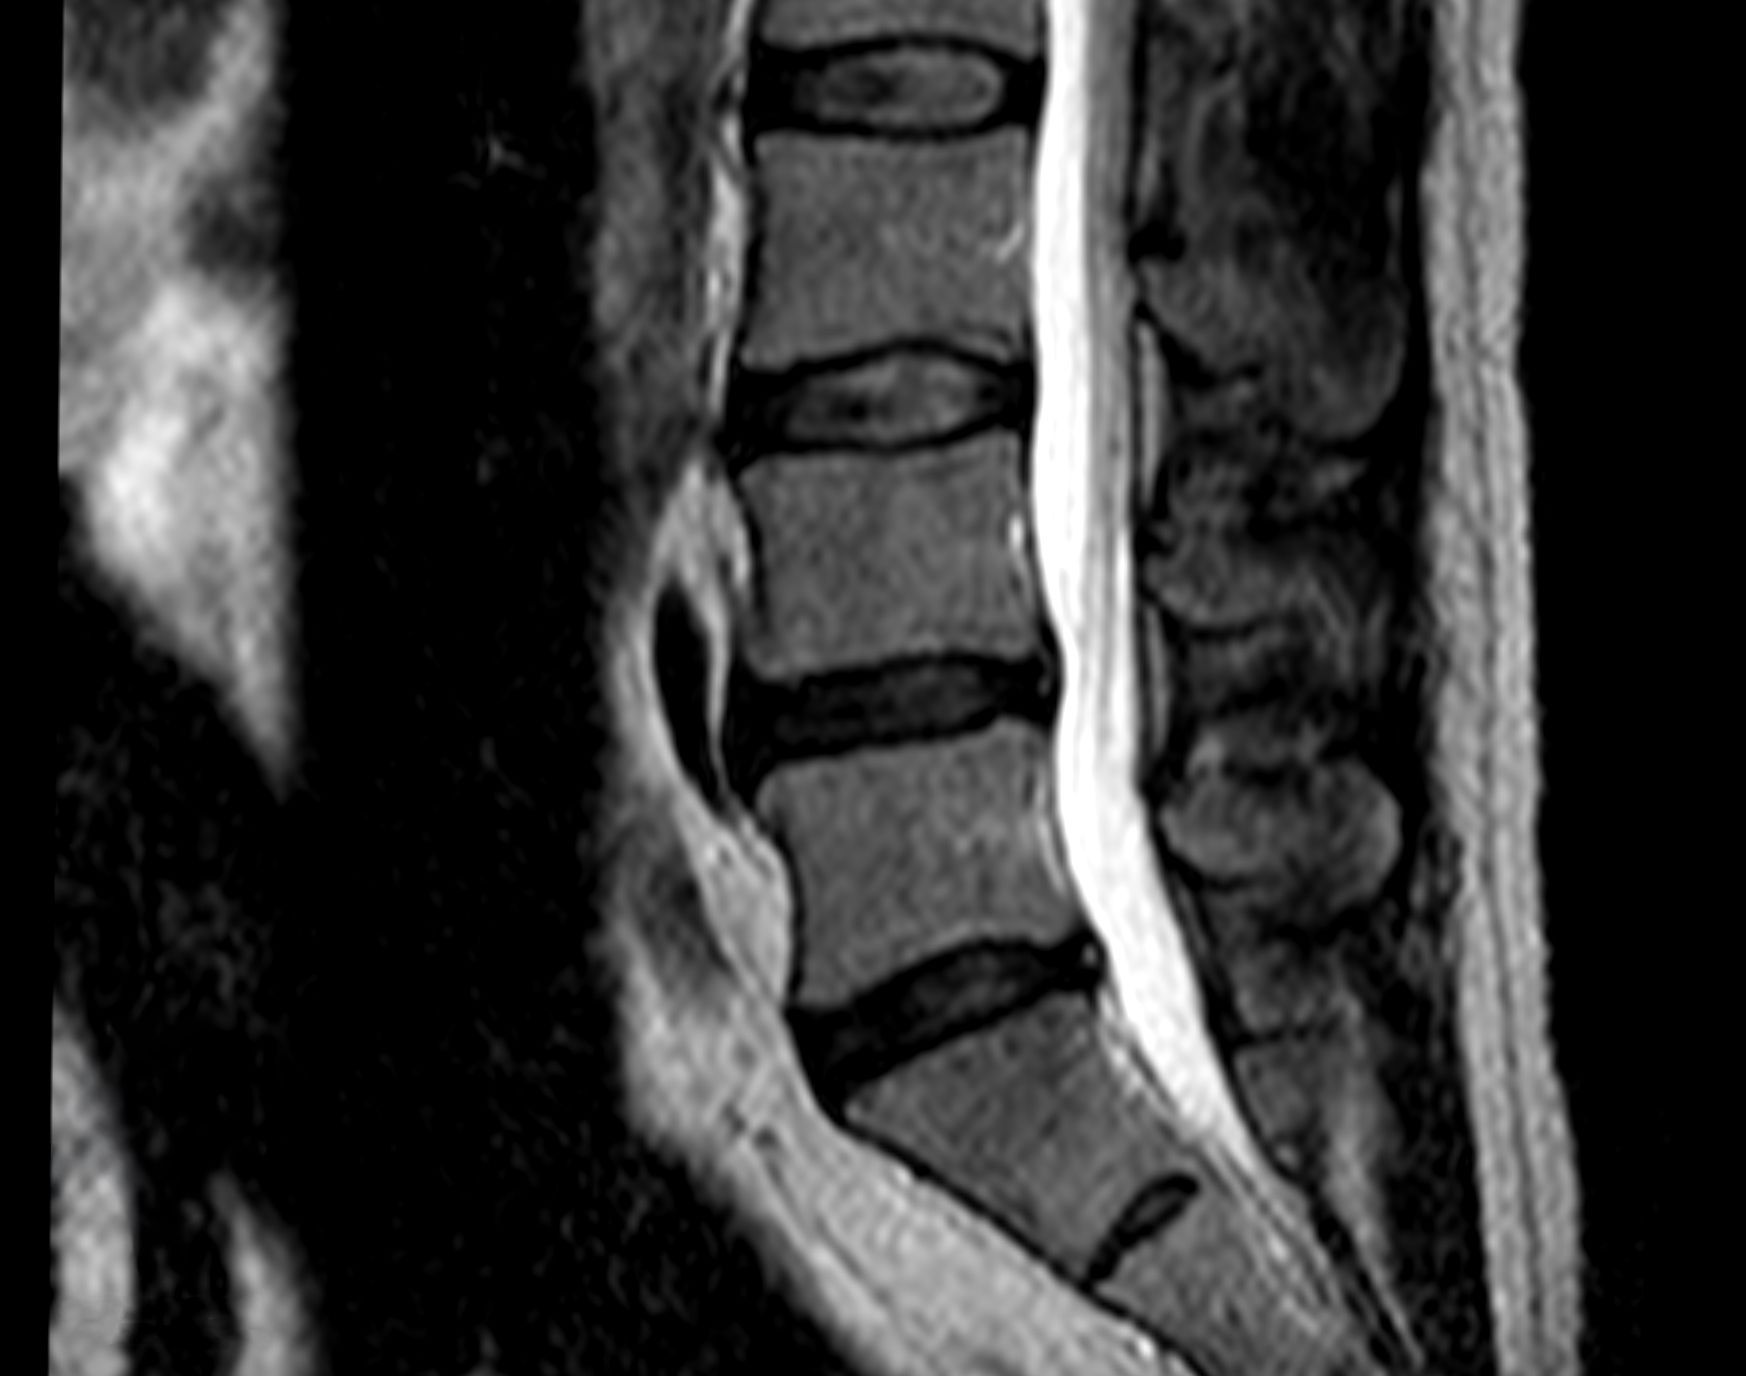

Cas clinique 2

Diagnostic

Patient de sexe masculin, âgé de 68 ans. Symptômes : Douleur lombaire gauche intense et invalidante ; le patient présente des difficultés de mouvement et de marche. Diagnostic : Hernie discale postéro-latérale gauche en L4-L5.